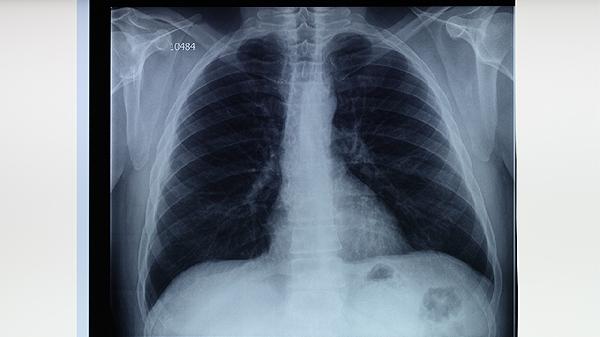

影像科不直接接诊患者,但对肺结节诊断至关重要。高分辨率CT能显示结节密度、钙化等特征,PET-CT可鉴别良恶性。复查结节变化时需固定设备参数,由同一影像科医生对比评估。肺结核治愈后遗留的纤维灶也需定期影像随访。